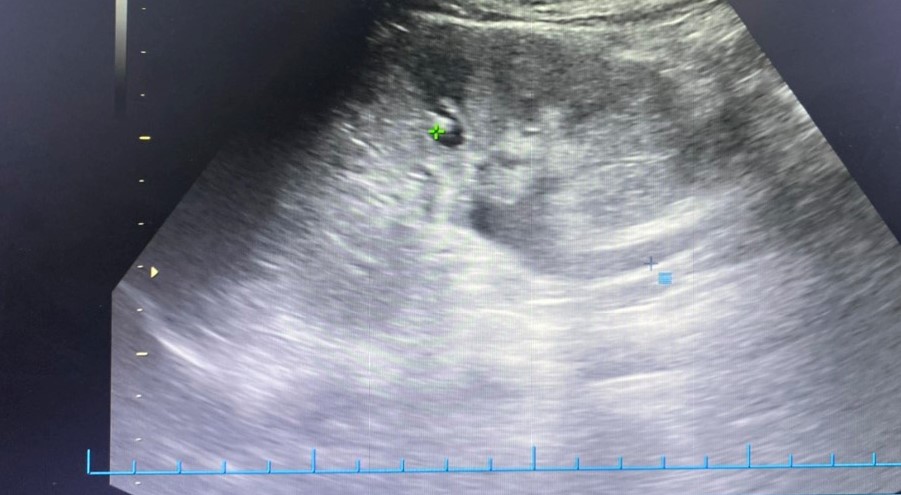

Bệnh nhân M.N, 31 tuổi ở quận Hải An, Hải Phòng vào Bệnh viện đa khoa Quốc tế Hải Phòng trong tình trạng đau mạn sườn phải, đau tăng dần lan xuống hạ vị ở tuần thai 31. Qua thăm khám và các chỉ định cận lâm sàng cần thiết, bác sĩ phát hiện người bệnh có sỏi niệu quản 1/3 trên, viêm thận bể thận phải, thận giãn độ 2, các chỉ số viêm nhiễm tăng cao. Bệnh nhân được điều trị nội khoa nhưng tình trạng đau nhiều không đỡ, sốt, tiểu buốt, rắt. Sỏi niệu quản khá to, kết hợp tuần thai lớn gây chèn ép niệu quản, điều trị nội khoa không hiệu quả cùng các biến chứng nguy hiểm như nhiễm trùng, giãn thận, viêm thận… có thể gây nguy hiểm cho cả mẹ và thai nhi. Trước tình trạng thai phụ như vậy các bác sĩ Khoa Ngoại thận tiết niệu – Nam học đã rất cân nhắc và hội chẩn để đưa ra quyết định nội soi tán sỏi niệu quản cho bệnh nhân. Kết quả tán sỏi thành công, bệnh nhân và thai nhi đều an toàn.

Ở trường hợp khác, bệnh nhân L.C, 28 tuổi vào Khoa cấp cứu, Bệnh viện đa khoa Quốc tế Hải Phòng trong tình trạng cơn đau quặn thận trái ở tuần thai 26. Bác sĩ cũng phát hiện bệnh nhân có sỏi niệu quản trái sát thành bàng quang, sỏi thận nhỏ 2 bên, thận giãn độ 1, hội chứng nhiễm trùng. Các phương pháp điều trị nội khoa không hiệu quả, bệnh nhân được thực hiện nội soi tán sỏi niệu quản. Trong suốt quá trình thực hiện, kíp thực hiện đã vô cùng thận trọng để đảm bảo an toàn cho cả thai phụ và thai nhi. Ca phẫu thuật được thực hiện rất thành công, viên sỏi đã được tán hết. Sau mổ, người bệnh đã hết đau, sức khỏe thai nhi hoàn toàn ổn định.

Theo TS.BSNT Phạm Việt Hà – Giám đốc chuyên môn hệ Ngoại, Bệnh viện đa khoa Quốc tế Hải Phòng chia sẻ: Thai phụ có kèm sỏi tiết niệu sẽ rất khó trong cả chẩn đoán và phẫu thuật bởi phụ nữ mang thai chỉ có thể áp dụng siêu âm mà không chụp Xquang hay CT. Cạnh đó, khi phẫu thuật, thai chèn ép gây khó khăn cho việc đưa ống soi lên niệu quản và vào bể thận; khó khăn trong việc sử dụng thuốc nhất là thuốc tê, thuốc gây mê vì có nguy cơ ảnh hưởng đến thai nhi. Tuy nhiên, phẫu thuật nội soi tán sỏi được ghi nhận là phương pháp ít xâm lấn, không có vết mổ và rất an toàn, bệnh nhân hồi phục nhanh chóng, đảm bảo an toàn cho sản phụ và thai nhi. Thai phụ khi có sỏi đường tiết niệu cần đến cơ sở y tế có đầy đủ trang thiết bị và đội ngũ y tế chuyên sâu về sản khoa và phẫu thuật tiết niệu để được thăm khám, phát hiện bệnh, điều trị kịp thời và hiệu quả.